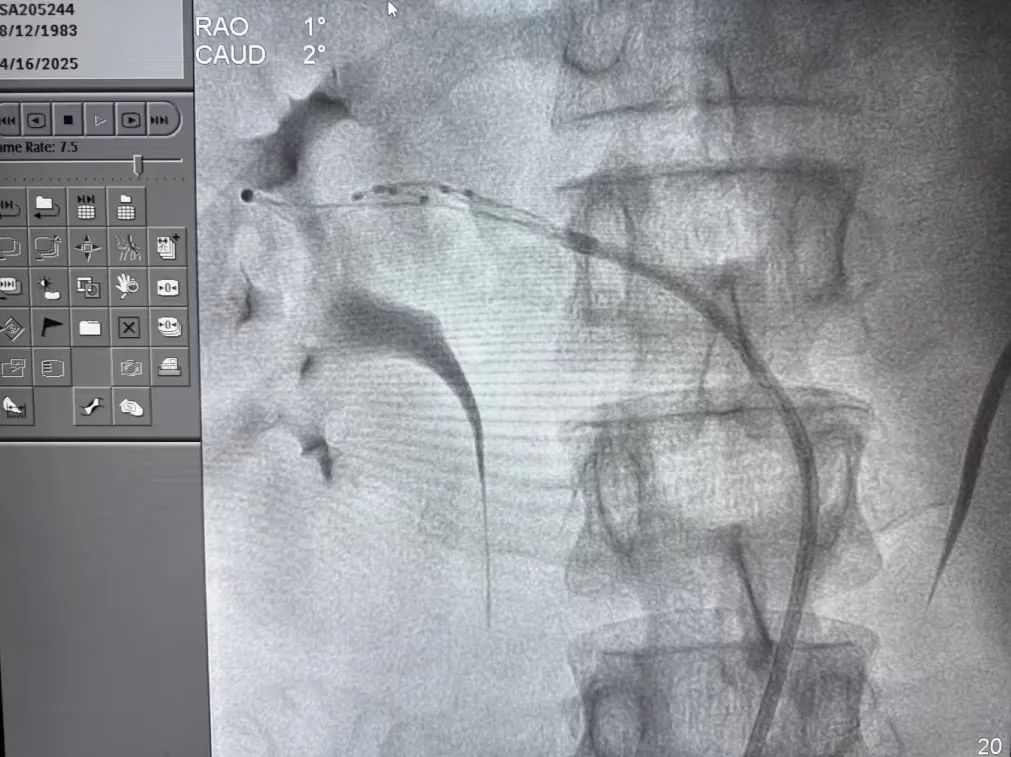

近日,周先生再次来到杭州市第一人民医院心血管内科复诊。经过钟益刚主任团队的全面评估,最终确定为难治性原发性高血压。考虑到患者对多种降压药物反应不佳,专家团队决定采用创新性的经皮去肾神经术(RDN)治疗方案。

RDN技术的原理在于通过射频消融抑制肾动脉周围过度活跃的交感神经。这些神经的异常兴奋会激活肾素-血管紧张素-醛固酮系统,导致持续性血压升高。该技术具有创伤小、恢复快、长期效果稳定等特点,为难治性高血压患者提供了全新的治疗选择。